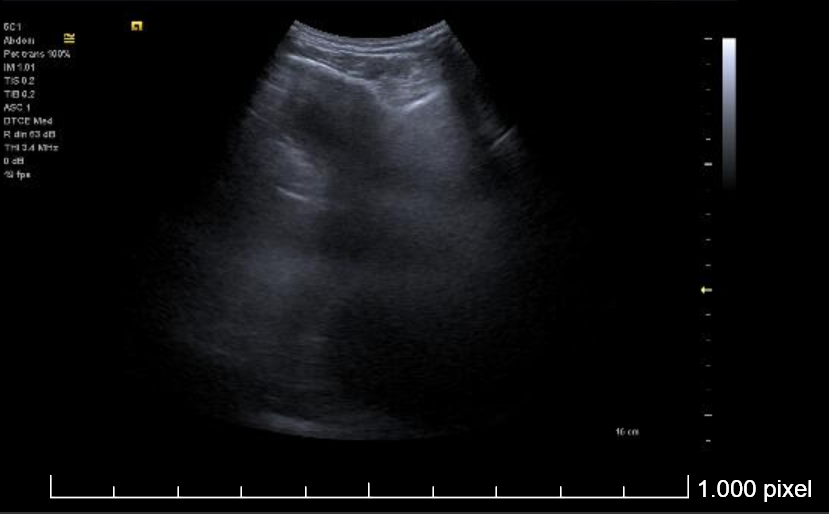

Ecografía torácica:

Derrame pleural izquierdo de 4 espacios intercostales, libre, hipoecogénico, sin ecos internos. Lóbulo pulmonar inferior izquierdo con imagen de patrón mixto (Intersticial y consolidación).